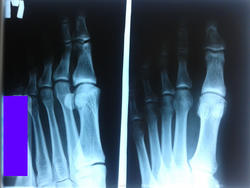

Доброе утро. Прошу помощи опытных... Описывая вчера снимок, обратил внимание на запись травматолога: Жалобы - на боли в I пальце; St.loc. - отек, кровоподтеки, болезненность в области фаланг I пальца правой стопы; Диагноз - "закрытый перелом головки основной фаланги I пальца правой стопы". Дело в том, что в нашей больнице рентгенолог не дежурит ночью и снимки сразу попадают к травматологу... Я перелома не увидел, что и указал в заключении.

Уважаемые внимательные опытные рентгенологи, подскажите, есть ли травматическое повре ждение? Чувствую, сегодня придет на меня сопеть травматолог.

Есть линия подозрительная на перелом, но с хорошим сроком. Для этого назначайте контроль через 7-10 дней и после лизиса увидите четкий перелом. Обязательно сравнивайте со старыми снимками. Если изменений нет, ну и с Богом отправьте больного.

На снимке в косой проекции определяется линия, подозрительная на перелом в головке основной фаланги 1пальца.